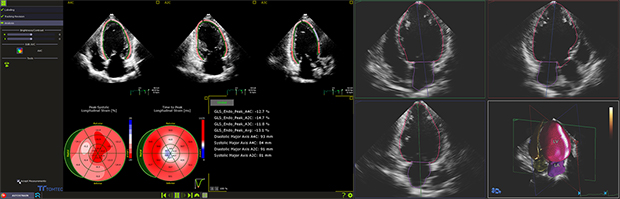

AI技術を活用した自動化機能で検査の効率化

GLS(Global Longitudinal Strain) 解析を行うAutoStrain LVでは,AI技術1により解析に必要な3断面を自動選択する Smart View Selectに対応します。